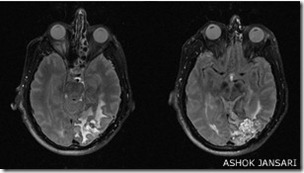

"Esto es extremadamente raro, pues el tipo de daño que debe ocurrir en el cerebro es muy específico", le cuenta a BBC Mundo el doctor Ashok Jansari, experto en el trastorno y lector en Neuropsicología Cognitiva de la Facultad de Psicología de la Universidad de East London.

Este trastorno también puede ocurrir como resultado de una lesión cerebral, como. Este tipo de prosopagnosia se conoce como "prosopagnosia adquirida".

Expertos creen que una parte particular del cerebro está implicada específicamente en el procesamiento y el reconocimiento de caras. Esta parte se llama el área fusiforme facial.